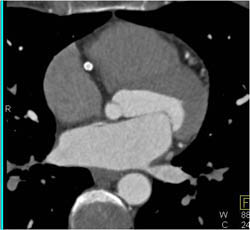

Right Coronary Artery Arises Off the Left Cusp